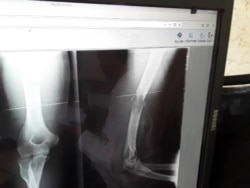

Imagen muestra la fractura sufrida por Pérez Carmenate. (Foto: Carlos Amel Oliva)

El activista, que cumple una condena de un año y cuatro meses por el delito de desobediencia, fue golpeado en plena calle el 12 de agosto pasado por agentes de la policía.

Pérez Carmenate permaneció 40 días sin asistencia médica en prisión hasta que fue operado de la lesión en un brazo, el 8 de octubre, en el hospital Clínico Quirúrgico de Las Tunas, y luego regresado a prisión.